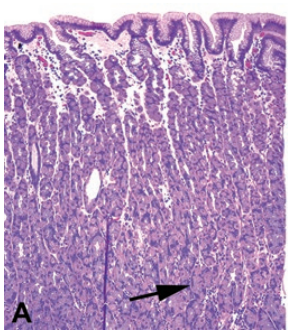

Oxyntic mucosa is relatively thick, with most of the mucosa occupied by secretory cells (arrow), the parietal and chief cells. The surface is composed of mucinous foveolar epithelium.

Antral mucosa is thinner, and the glands are mucinous instead of secretory (arrow). However, the surface is still composed of foveolar epithelium (arrowhead).